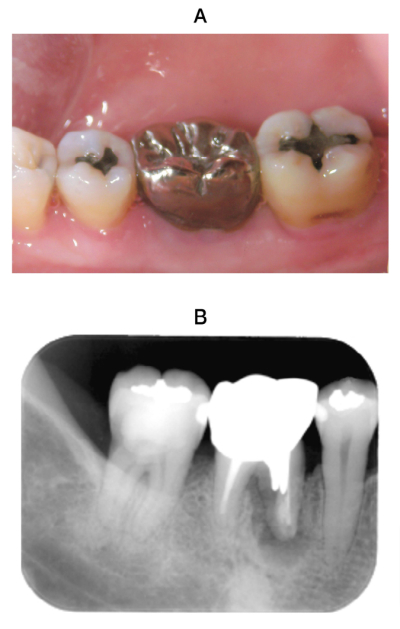

44 歳の女性。下顎右側大臼歯部の違和感を主訴として来院した。歯周基本治療後の再評価の結果、歯周外科治療を行うこととした。再評価時の舌面観の口腔内写真とエックス線画像を別に示す。再評価時の歯周組織検査結果の一部を表に示す。

6⏋の治療方針として適切なのはどれか。1つ選べ。